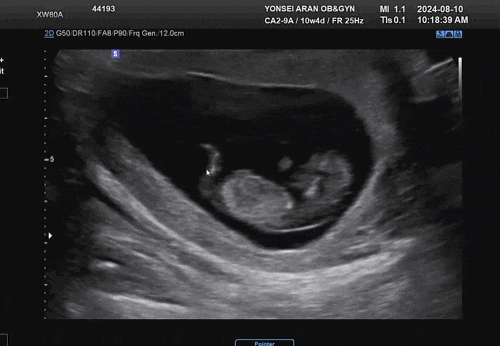

• • 24.08 임신 후 일상 ? [3주 4일] 3박 4일 출장을 앞두고 알게 된 임신 사실 아직 둘이 하고 싶은 ...

• • 24.09 임산부 일상 [12주 1일] 1차 기형아 검사를 잘 끝내고 감사했던 생일 주간도 잘 보낸 우리 ♡ ...